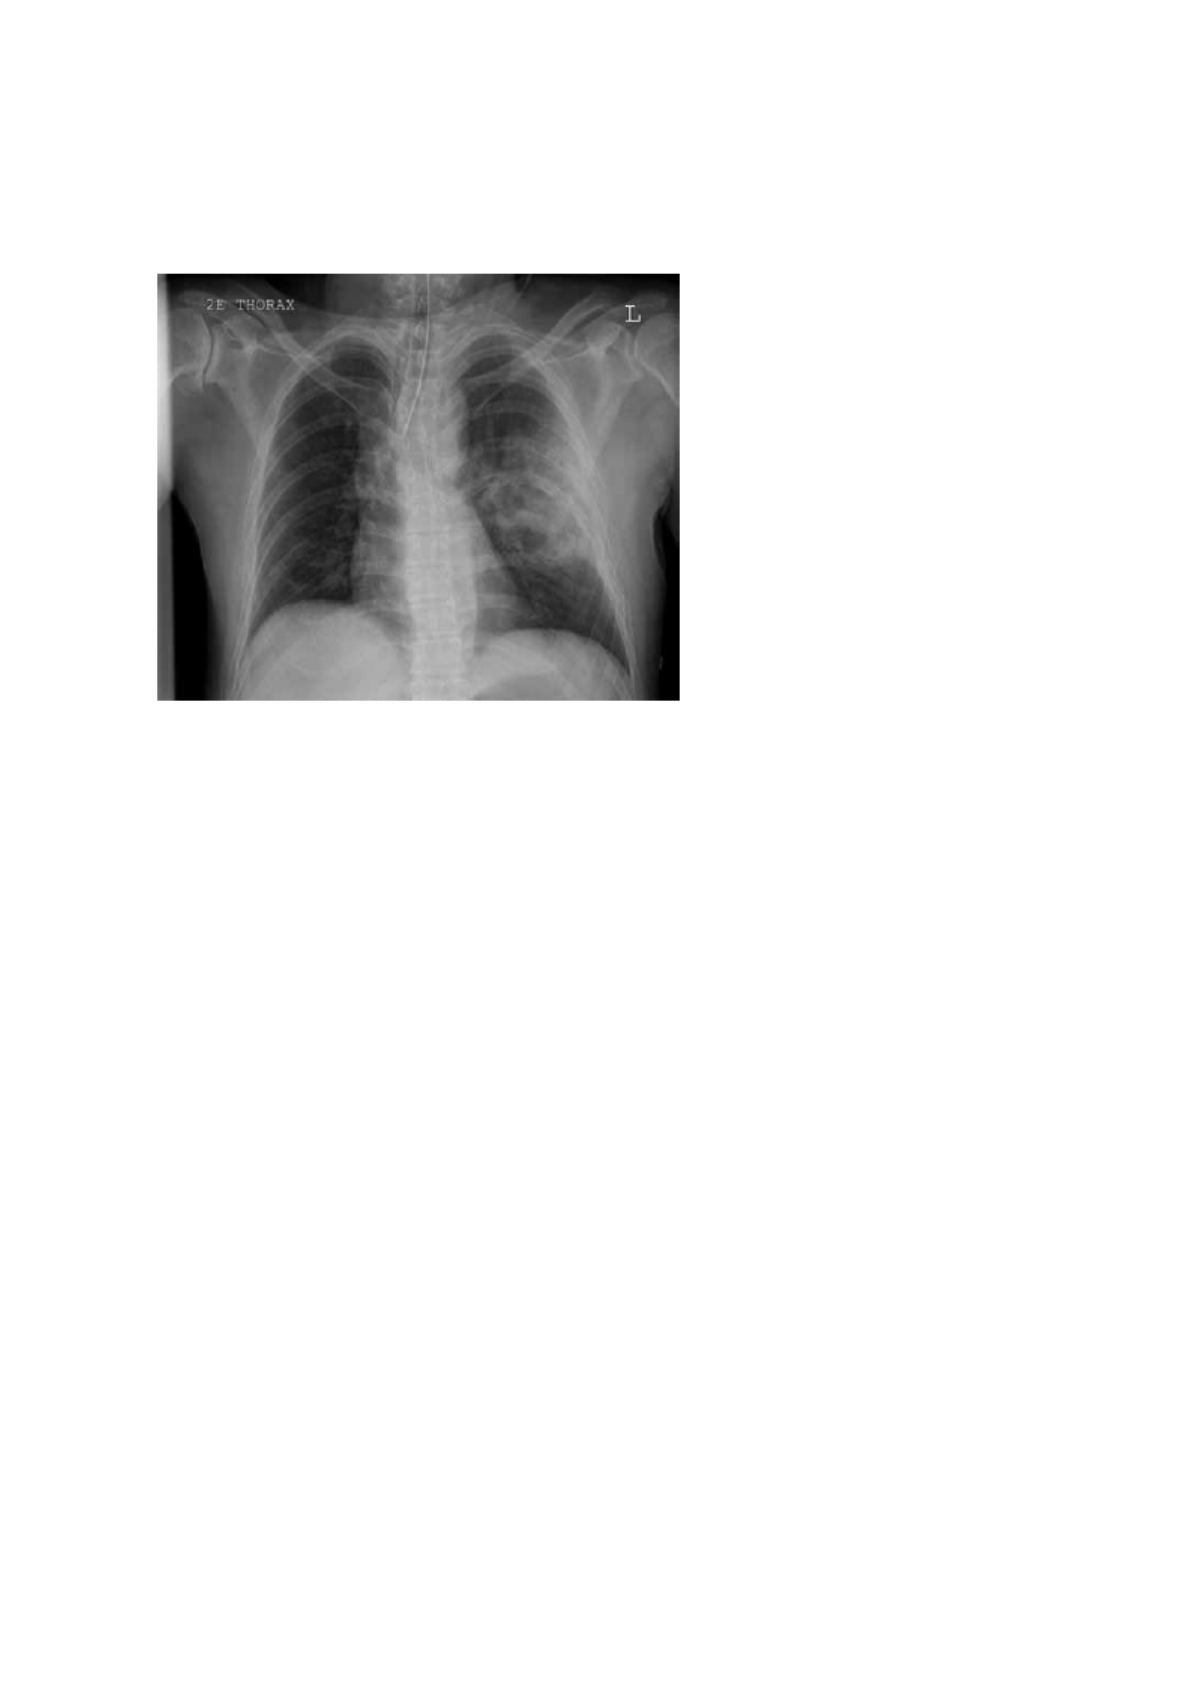

1. (VUNESP - 2019) Paciente de 18 anos, vítima de trauma, apresenta o r-X ilustrado a

seguir.

Nesse momento, é recomendável

A. punção de alívio no 2º espaço intercostal, linha hemiclavicular.

B. drenagem no tórax 5º espaço intercostal, linha axilar média

C. pericardiocentese.

D. toracotomia de emergência.

E. ventilação e oxigenação.

Resposta E - ventilação e oxigenação